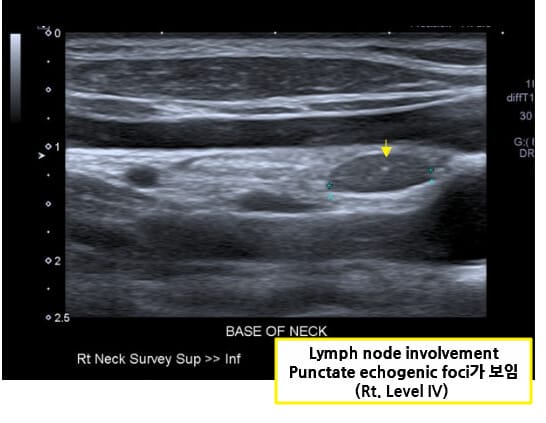

| 🔷 갑상선 전절제술 및 경부 림프절 절제술(Total thyroidectomy with neck dissection) |

| 진단 시 림프절 전이가 흔하므로 갑상선 전절제와 함께 림프절 절제를 시행합니다. |